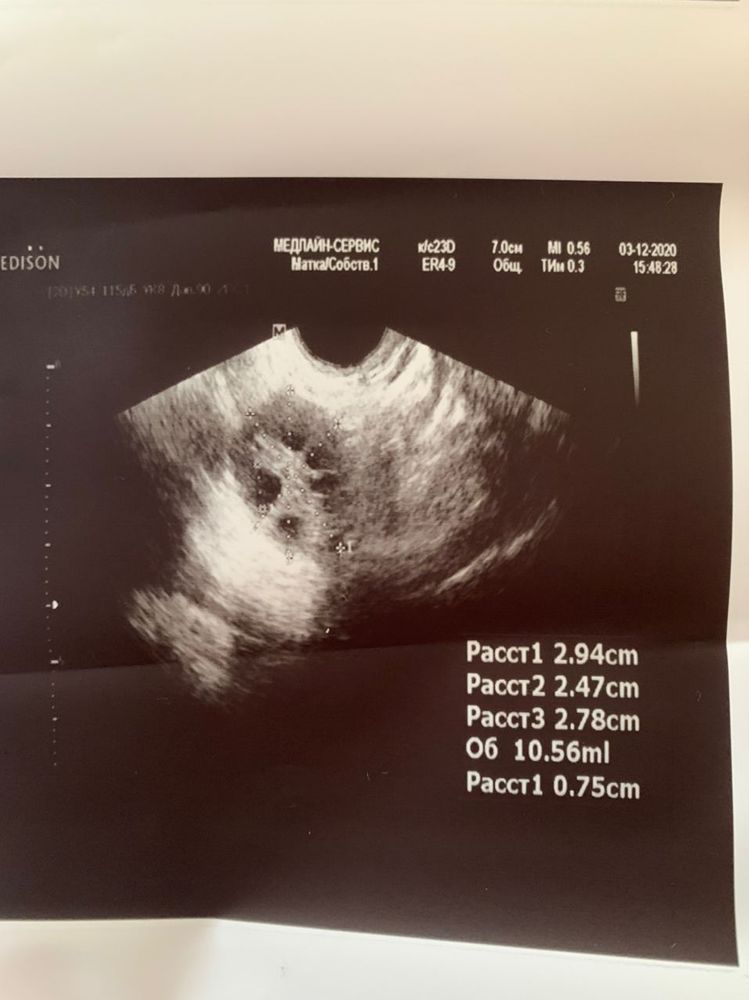

Пошла сегодня на фолликулометрию с полной уверенностью, что овуляция будет вот вот. А тут оказывается, у меня даже доминантного фолликула ни в одном яичнике нет.

У меня еще МФЯ, вот не знаю, есть шанс, что в этом цикле еще что-то будет или уже не на что надеяться?